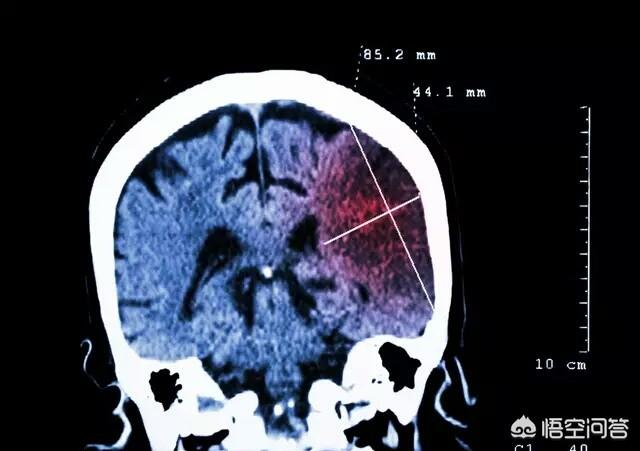

现阶段高死亡率的病不只癌症,还有心脑血管疾病。这个是现阶段人类第一大杀手。